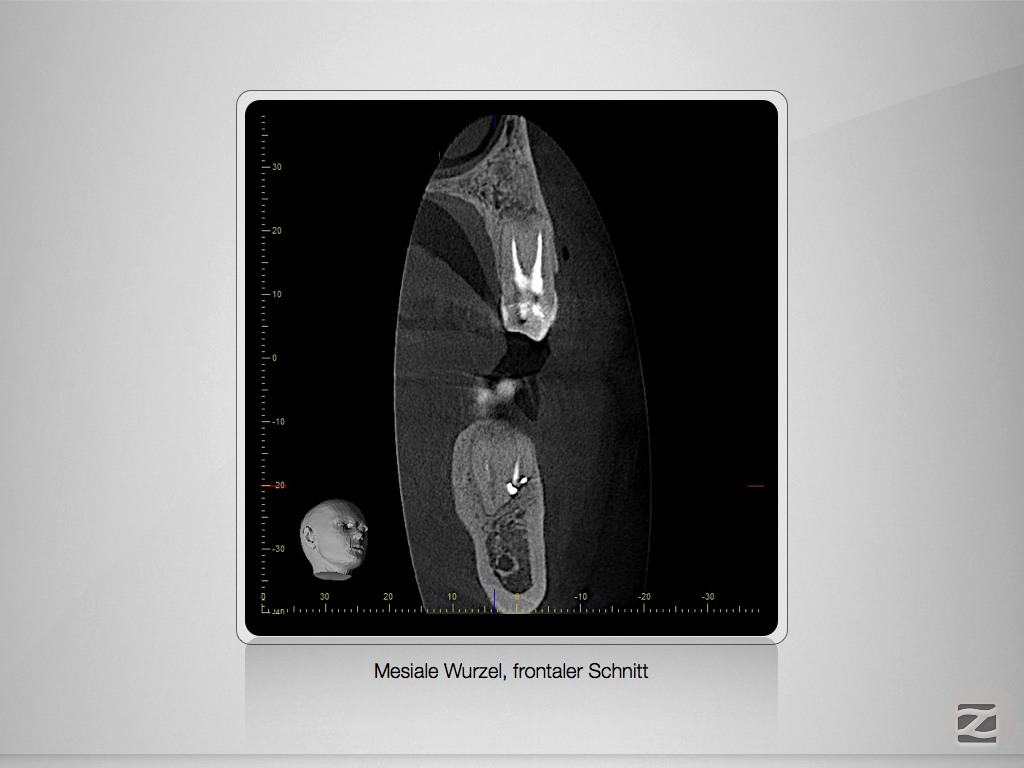

36D, 24D.004

2D vs. 3D – So habe ich entschieden